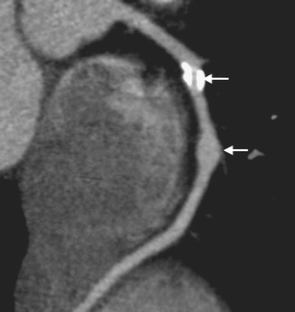

MSCT showed coronary artery injury in 15 of the 48 children. Among these 15 children, 20 coronary artery branches showed complications, including the left coronary artery branches in 15 (31.2%) and the right coronary artery branches in 5 (10.4%). Complications in the left coronary artery branches included dilation in 12 (25.0%) and stenosis, calcification and the combination of the two in one each, and the right coronary artery branches showed dilation; two branches also showed beaded changes. MSCT also showed dilation in the left anterior descending arteries in two children. These children showed no abnormality on 2-D echocardiography.

Fig. 2